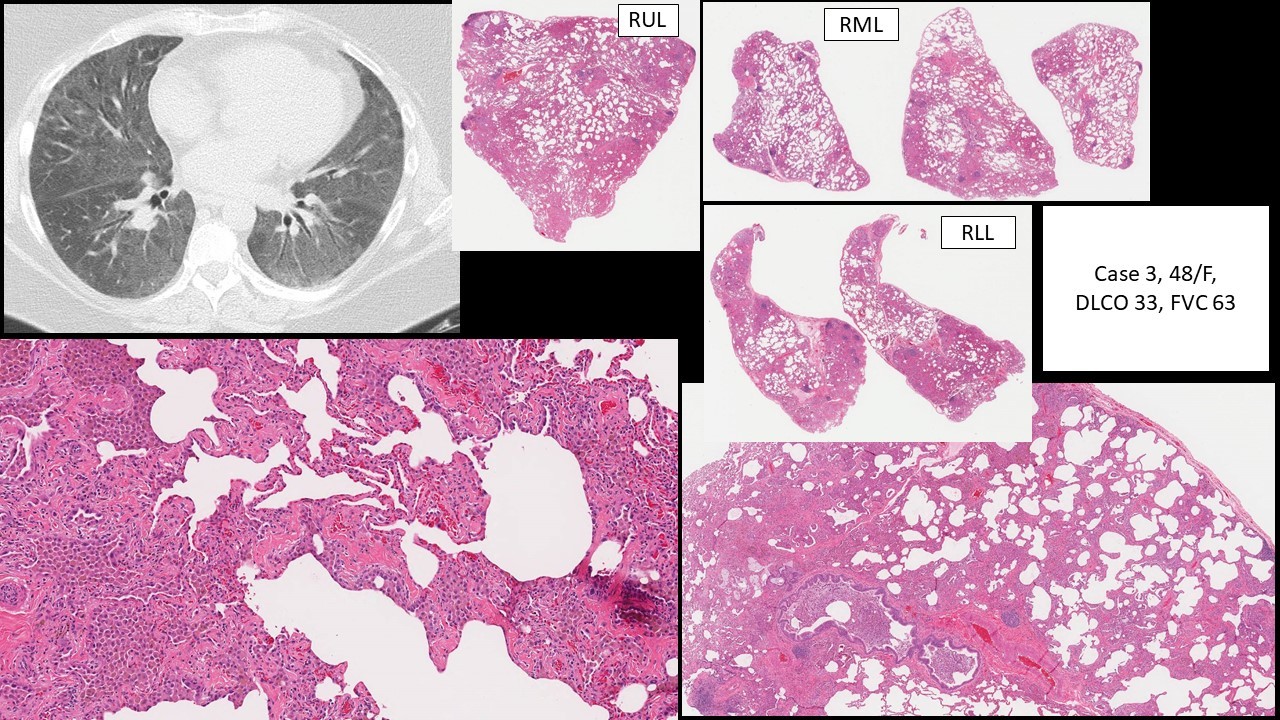

Smokingrelated interstitial fibrosis (SRIF) case 3 of the study/paper by Vehar S et al KiKo XP Smoking Related Fibrosis Radiology In addition smoking can also be a risk factor in other interstitial lung diseases such as: Fibrosis is also a common radiological feature ranging from sparse fibrosis along the alveolar walls, termed aef, to a. Radiologically, cpfe is recognized and characterized by the presence of emphysema predominantly in the upper lobes and. The combination of lower lung fibrosis and upper. Smoking Related Fibrosis Radiology.